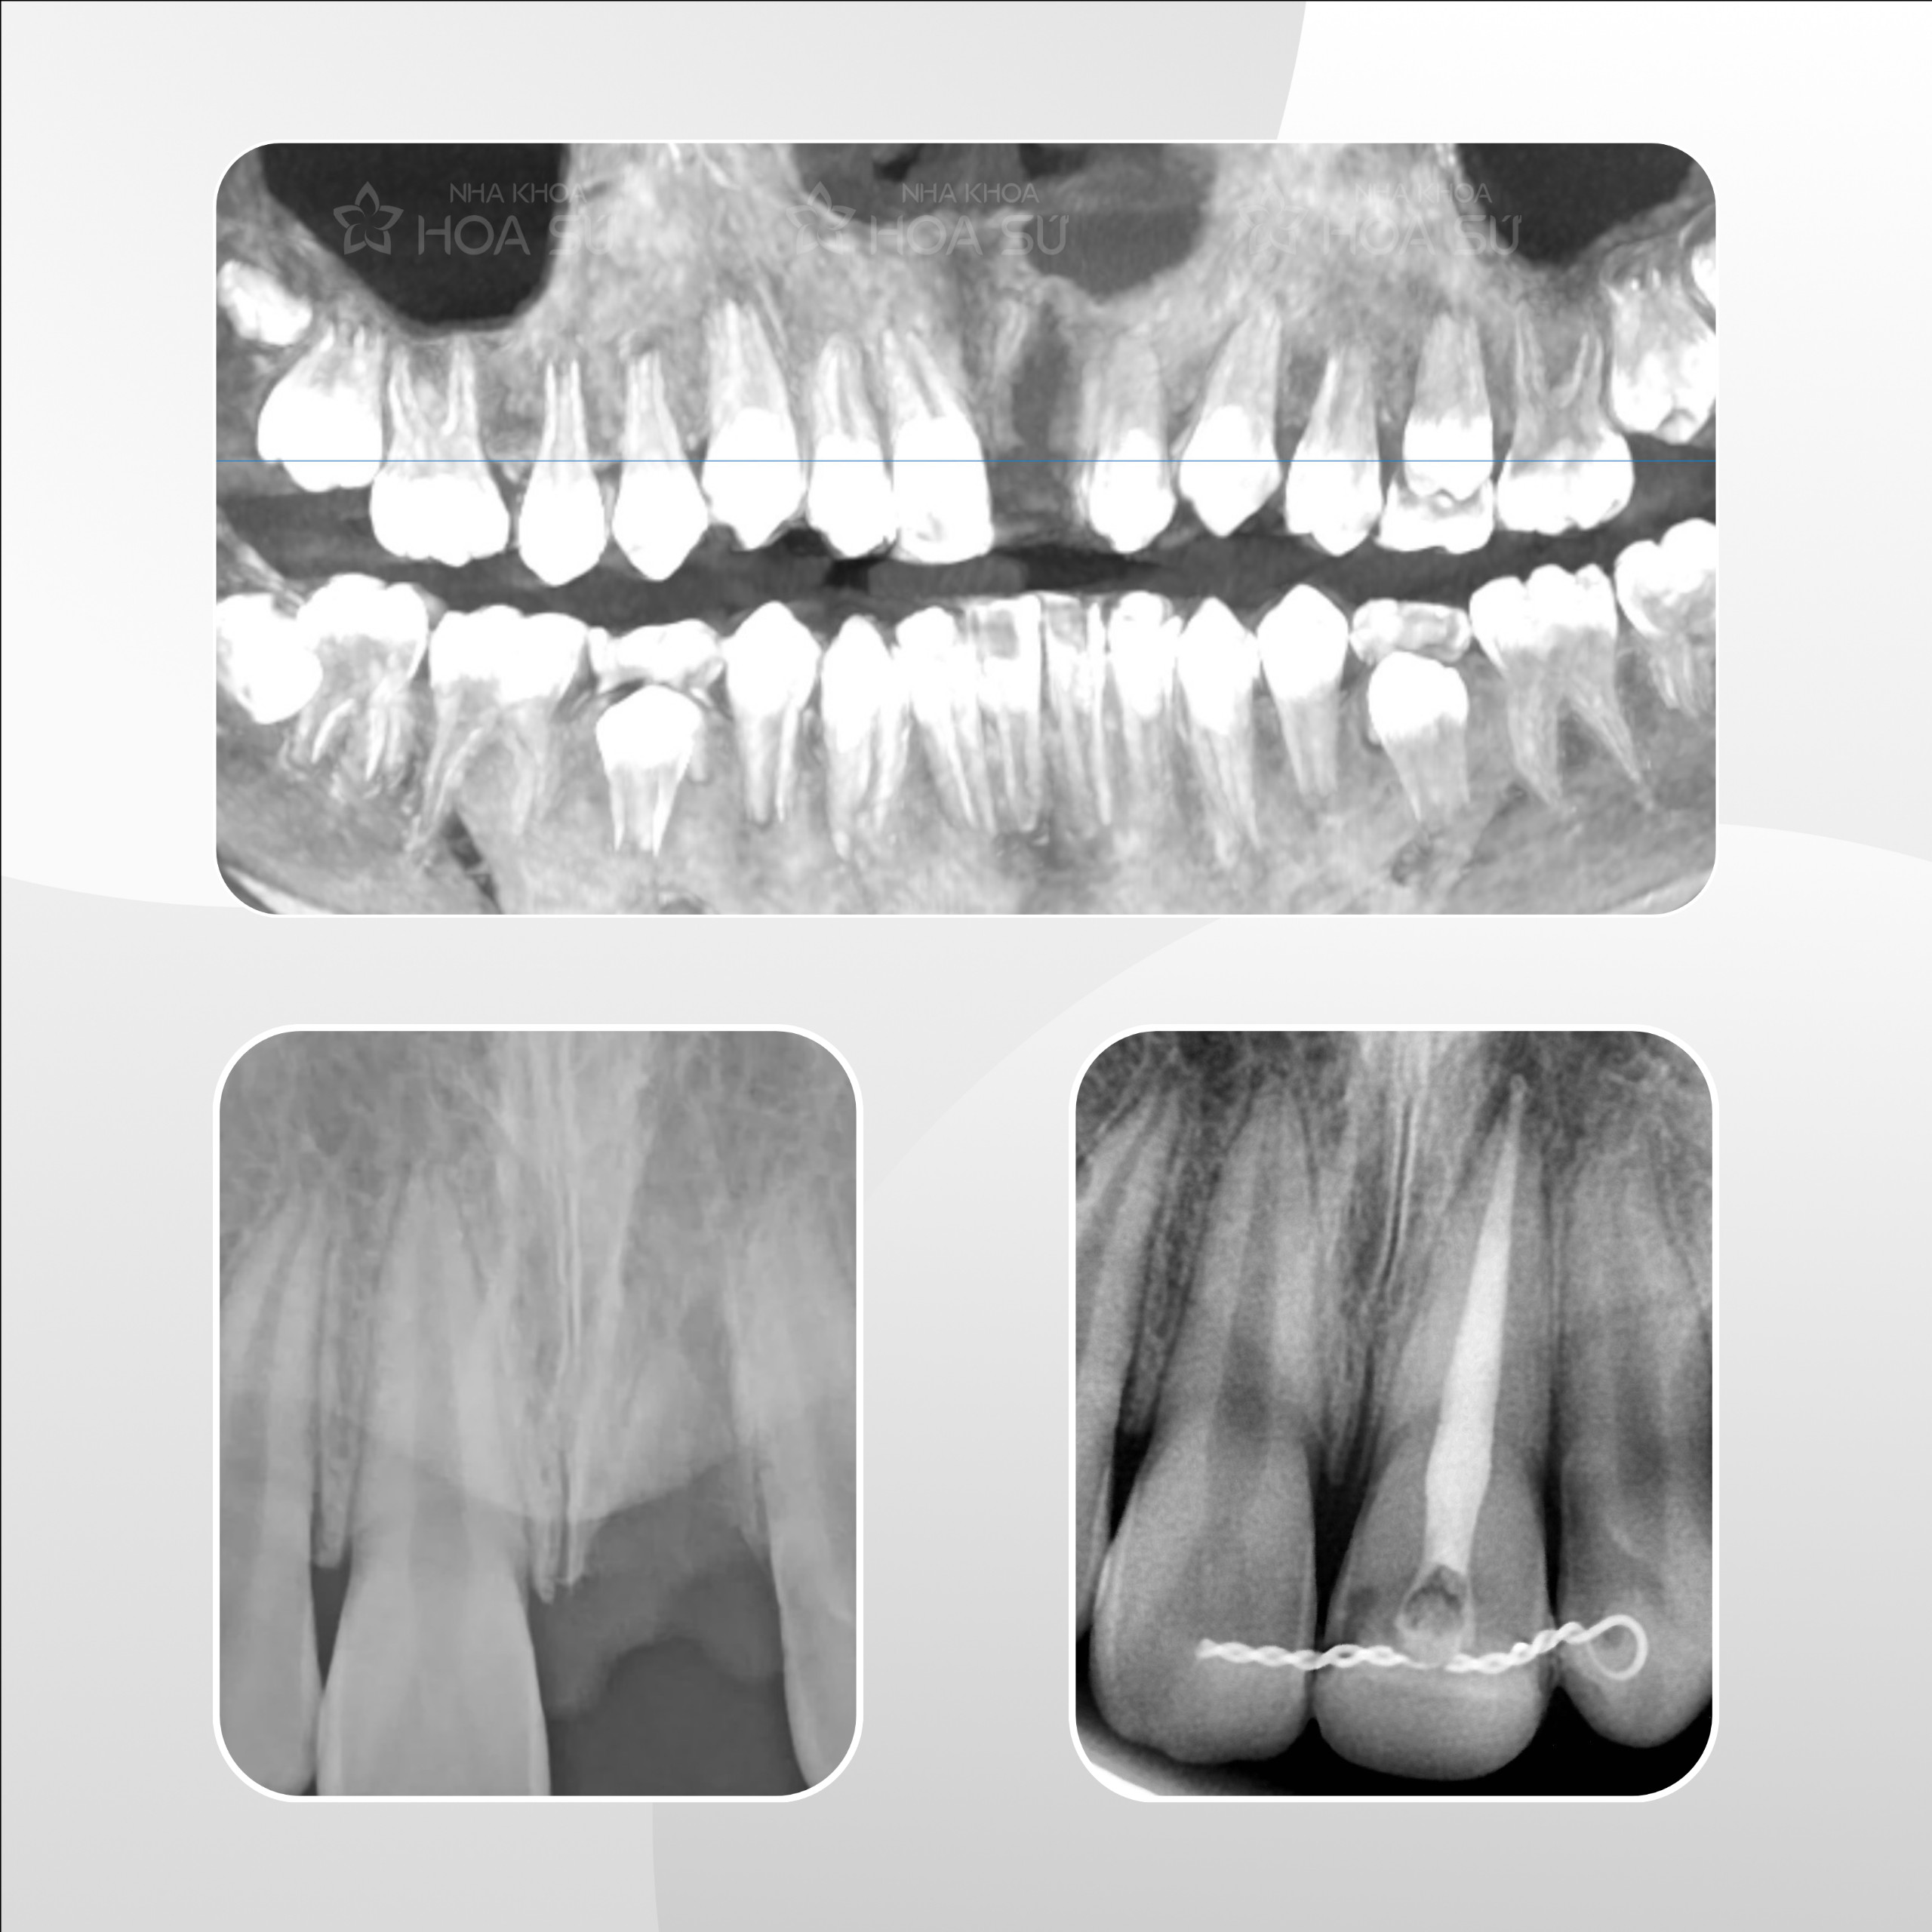

b8d8d7a1359a9ac4c38b Đã xuất bản Tháng 4 2, 2024 lúc 2560 × 2560 trong TRƯỜNG HỢP ĐẶC BIỆT: CẤP CỨU RĂNG RƠI RA NGOÀI Tiếp theo →